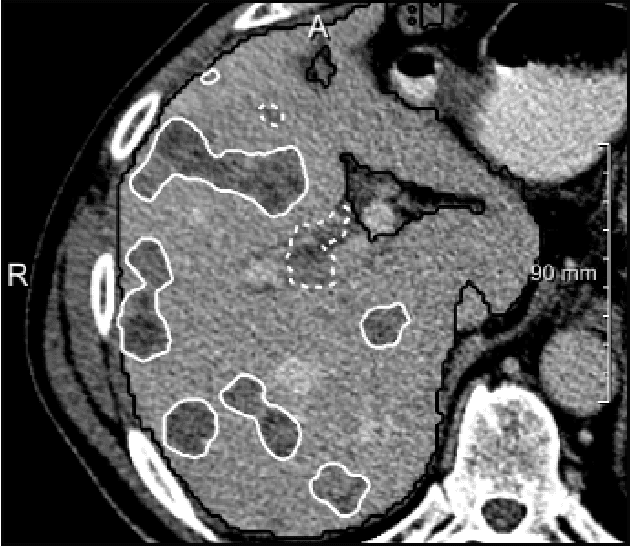

We present a fully automatic method employing convolutional neural networks based on the 2D U-net architecture and random forest classifier to solve the automatic liver lesion segmentation problem of the ISBI 2017 Liver Tumor Segmentation Challenge (LiTS). In order to constrain the ROI in which the tumors could be located, a liver segmentation is performed first. For the organ segmentation, an ensemble of convolutional networks is trained to segment a liver using a set of 179 liver CT datasets from liver surgery planning. Inside of the liver ROI a neural network, trained using 127 challenge training datasets, identifies tumor candidates, which are subsequently filtered with a random forest classifier yielding the final tumor segmentation. The evaluation on the 70 challenge test cases resulted in a mean Dice coefficient of 0.65, ranking our method in the second place.